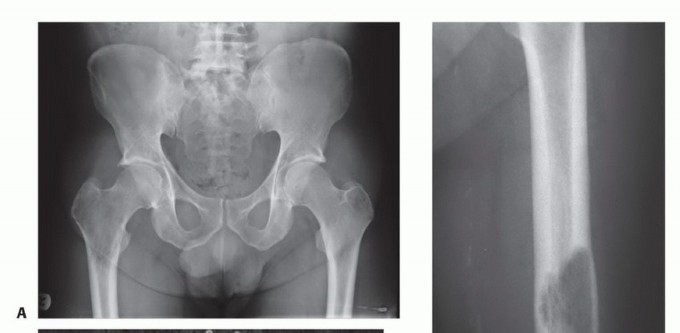

الشكل 2: أ. صورة أشعة سينية تظهر كسرًا مرضيًا في الورك لدى أنثى تبلغ من العمر 69 عامًا ولديها تاريخ معروف بسرطان الثدي. ب. أجريت عملية استبدال نصفي للورك خلال 24 ساعة من حدوث الكسر، ولكن صور الأشعة السينية بعد الجراحة أظهرت نقيلة إضافية أسفل طرف جذع الطرف الاصطناعي (ج) لم يتم اكتشافها بسبب سوء جودة صور الأشعة السينية قبل الجراحة ولأن صور الأشعة السينية للعظم بالكامل لم تُجرَ قبل الجراحة. د. بينما كانت لا تزال في المستشفى، عانت من كسر مرضي في تلك الآفة أثناء نقلها من سريرها إلى كرسي استلقاء.